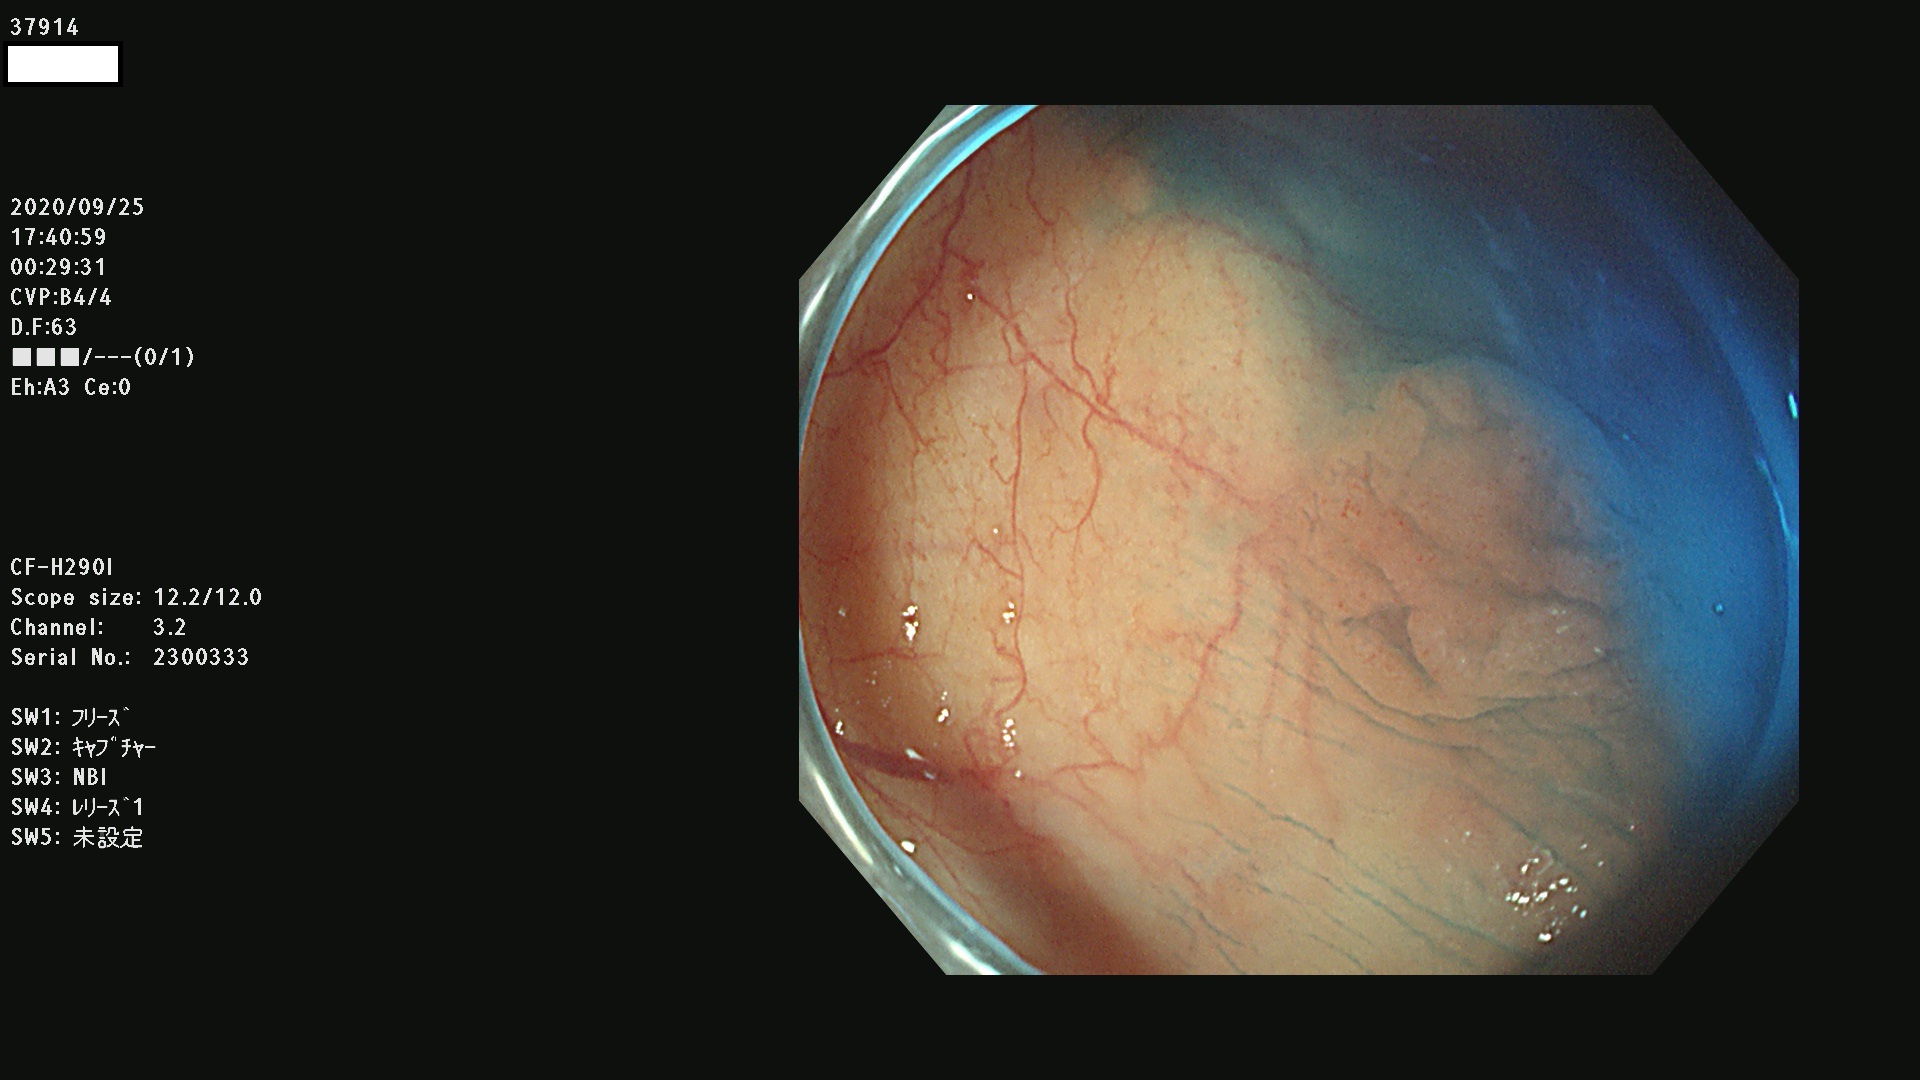

37900 37902 37903 37904 37905 37906 37907 37909 37910 37911 37912 37913 37914 37915 37916 37917 37919 37921 37922 37923 37926 37928 37929 37930 37931 37933 37934 37935 37936 37937 37938(SSAPのみ) 37939 37940 37941 37942 37943 37946 37947 37948 37949 37951 37952 37953(SSAPのみ) 37955 37956 37957(SSAPのみ) 37958(SSAPのみ) 37960 37962 37963 37964 37966 37967 37968 37971 37972 37973 37975 37976 37977 37979 37982 37983 37984 37985 37986 37987 37988 37989 37990 37991 37992 37993 37994 37995 37996 37998 37999

発見困難で危険性の高い平坦型病変(上記100名より抽出)